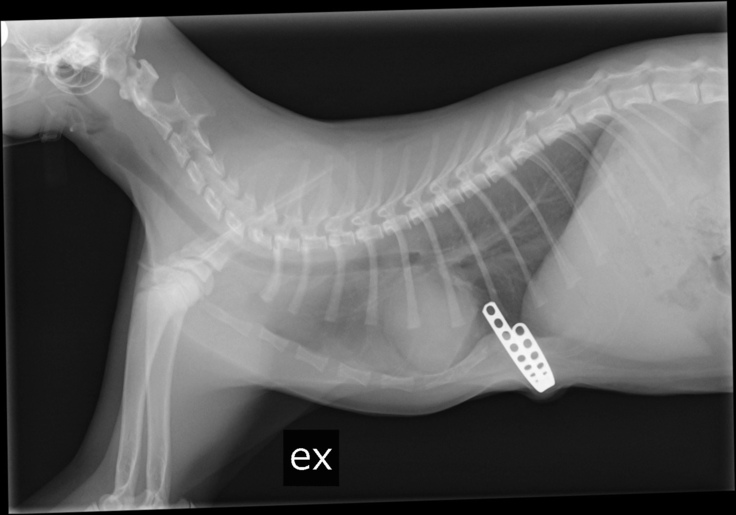

こちらは本日撮影したレントゲン写真です。

胸の凹みが少なくなってきています。